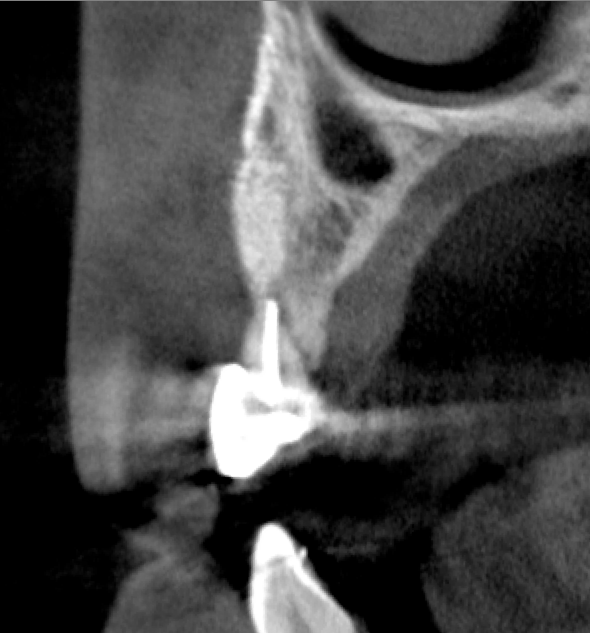

Tomographic images revealed a large tridimensional defect, with vertical and horizontal loss of bone extending to the apical third of teeth Nos. 6 and 8. Additionally, a buccal bone dehiscence was evident on tooth No. 5, and thin labial plates secondary to the orthodontic movement were present in several areas (Figure 3 and Figure 4).

After 3 months of post-orthodontic stabilization, a cone-beam computed tomography scan was taken to re-evaluate the results and plan the future treatment sequence. Tomographic images clearly showed vertical gains in alveolar height, including in the edentulous area corresponding to tooth No. 7 (Figure 10 through Figure 12). The apex of tooth No. 8 was forced-erupted beyond its socket and could be visibly located within the soft tissue.30,33